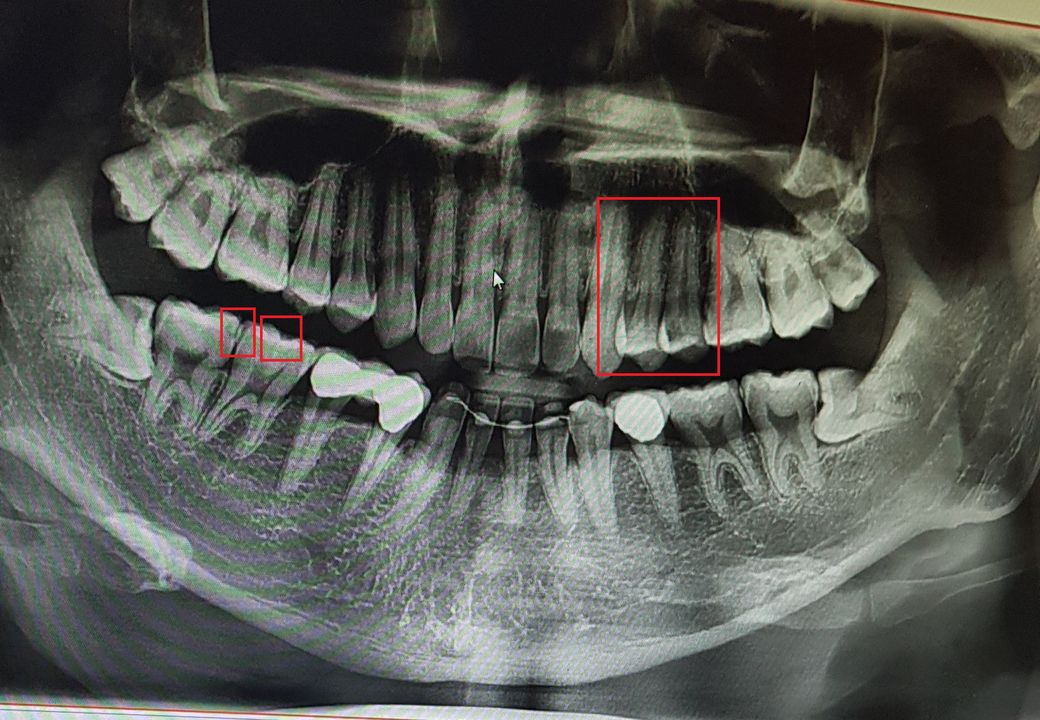

인접면 충치 xray 봐주실수 있나요

일단 오른쪽 위에 오른쪽 치아가 인접면 충치가 발생해서 인레이 치료를 했습니다.

도중 옆치아에도 살짝 갈색처럼 돼 있어서 옆치아도 같이 인레이 치료를 하기를 권장해서 그렇게 했는데 첫 치아 인레이 도중 피가 나왔다고 신경까지 치료해야겠다고 해서 동의를 하고 신경치료 후 크라운까지 하기로 했는데요.

Xray상으로 신경까지 충치가 번졌는지 알 수 없는건가요?

왼쪽아래의 어금니도 접합면 충치가 있어서 때울려고 했는데 인접면까지 충치가 있는 게 보인다고 인레이로 해야한다고 하더라구요. 인레이 도중 옆치아에도 충치가 있으면 그땐 레진으로 한다고 하는데 또 치아 두개를 인레이로 한다고 할 거 같은 느낌이 드는데..

• 인접면 충치는 해당 panorama 사진으로 정도를 평가하지 않습니다. 첨부해주신 사진은 전체적인 치아를 조망하는 사진이지 특정한 부위의 충치를 판단하는데 사용하지 않습니다. 정말 넓고 깊은 충치가 아니라면 대부분은 standard view를 통해 인접 충치를 평가해야 합니다. 따라서 말씀하신 사진으로는 정확한 평가가 어렵습니다.

• 파노라마 사진만 가지고 판별을 하는 것은 어려움이 있습니다. 인접면에 충치가 생긴 경우에는 주로 레진보다는 인레이를 이용합니다.